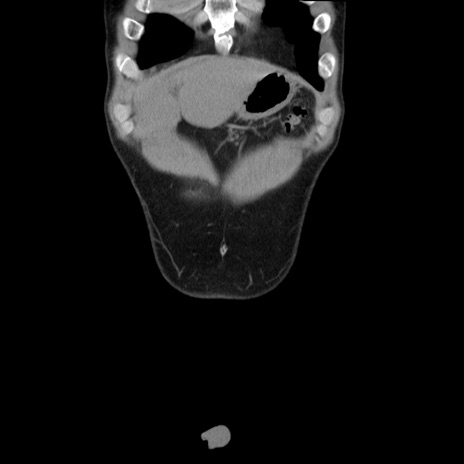

症例36(冠状断像)

【症例】20歳代 男性

【主訴】心窩部痛

【現病歴】今朝より上腹部痛あり。一旦軽快していたが再度出現したため救急要請。昨日夕に白身の魚を含む刺身を食べた。

【身体所見】BP 136/89mmHg、HR 74/min、BT 37.0℃、腹部:膨満、軟、心窩部に圧痛あり。反跳痛なし、筋性防御なし、腸雑音やや亢進あり。

【データ】WBC 17700、CRP 0.48